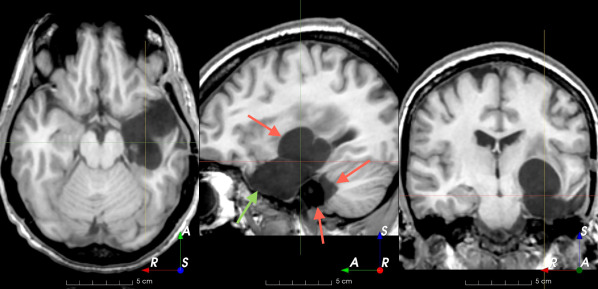

(f)

Figure 3: Manual labels from Rater A (green) and Rater D, the model trained with PubFull + EpiPre + Pseudo (magenta). Errors caused by a (a) small resection, (b) blood clot in cavity and (c) brain shift; segmentations corresponding to the (d) 50th, (e) 75th and (f) 100th percentiles giving a DSC of 81.7, 86.5 and 93.8, respectively.

We trained a model using PubFull, EpiPre and Pseudo (2371 images), obtaining a DSC of 81.7 (14.2). Adding the pseudo-labels to PubFull and EpiPre did not significantly improve performance (p=0.176𝑝0.176p=0.176), indicating our semi-supervised learning approach provided no advantage. Predictions from this model are shown in Fig. 3.

Predictions errors are mostly due to 1) resection of size comparable to sulci (Fig. 6a), 2) unanticipated intensities, such as those caused by the presence of blood clots in the cavity (Fig. 6b), 3) brain shift (Fig. 6c) and 4) white matter hypointensities (Fig. 6e). Further work will involve using different internal and external cavity textures, carefully sampling the resection volume, simulating brain shift using biomechanical models, and quantifying epistemic and aleatoric segmentation uncertainty to better assess model performance [24].